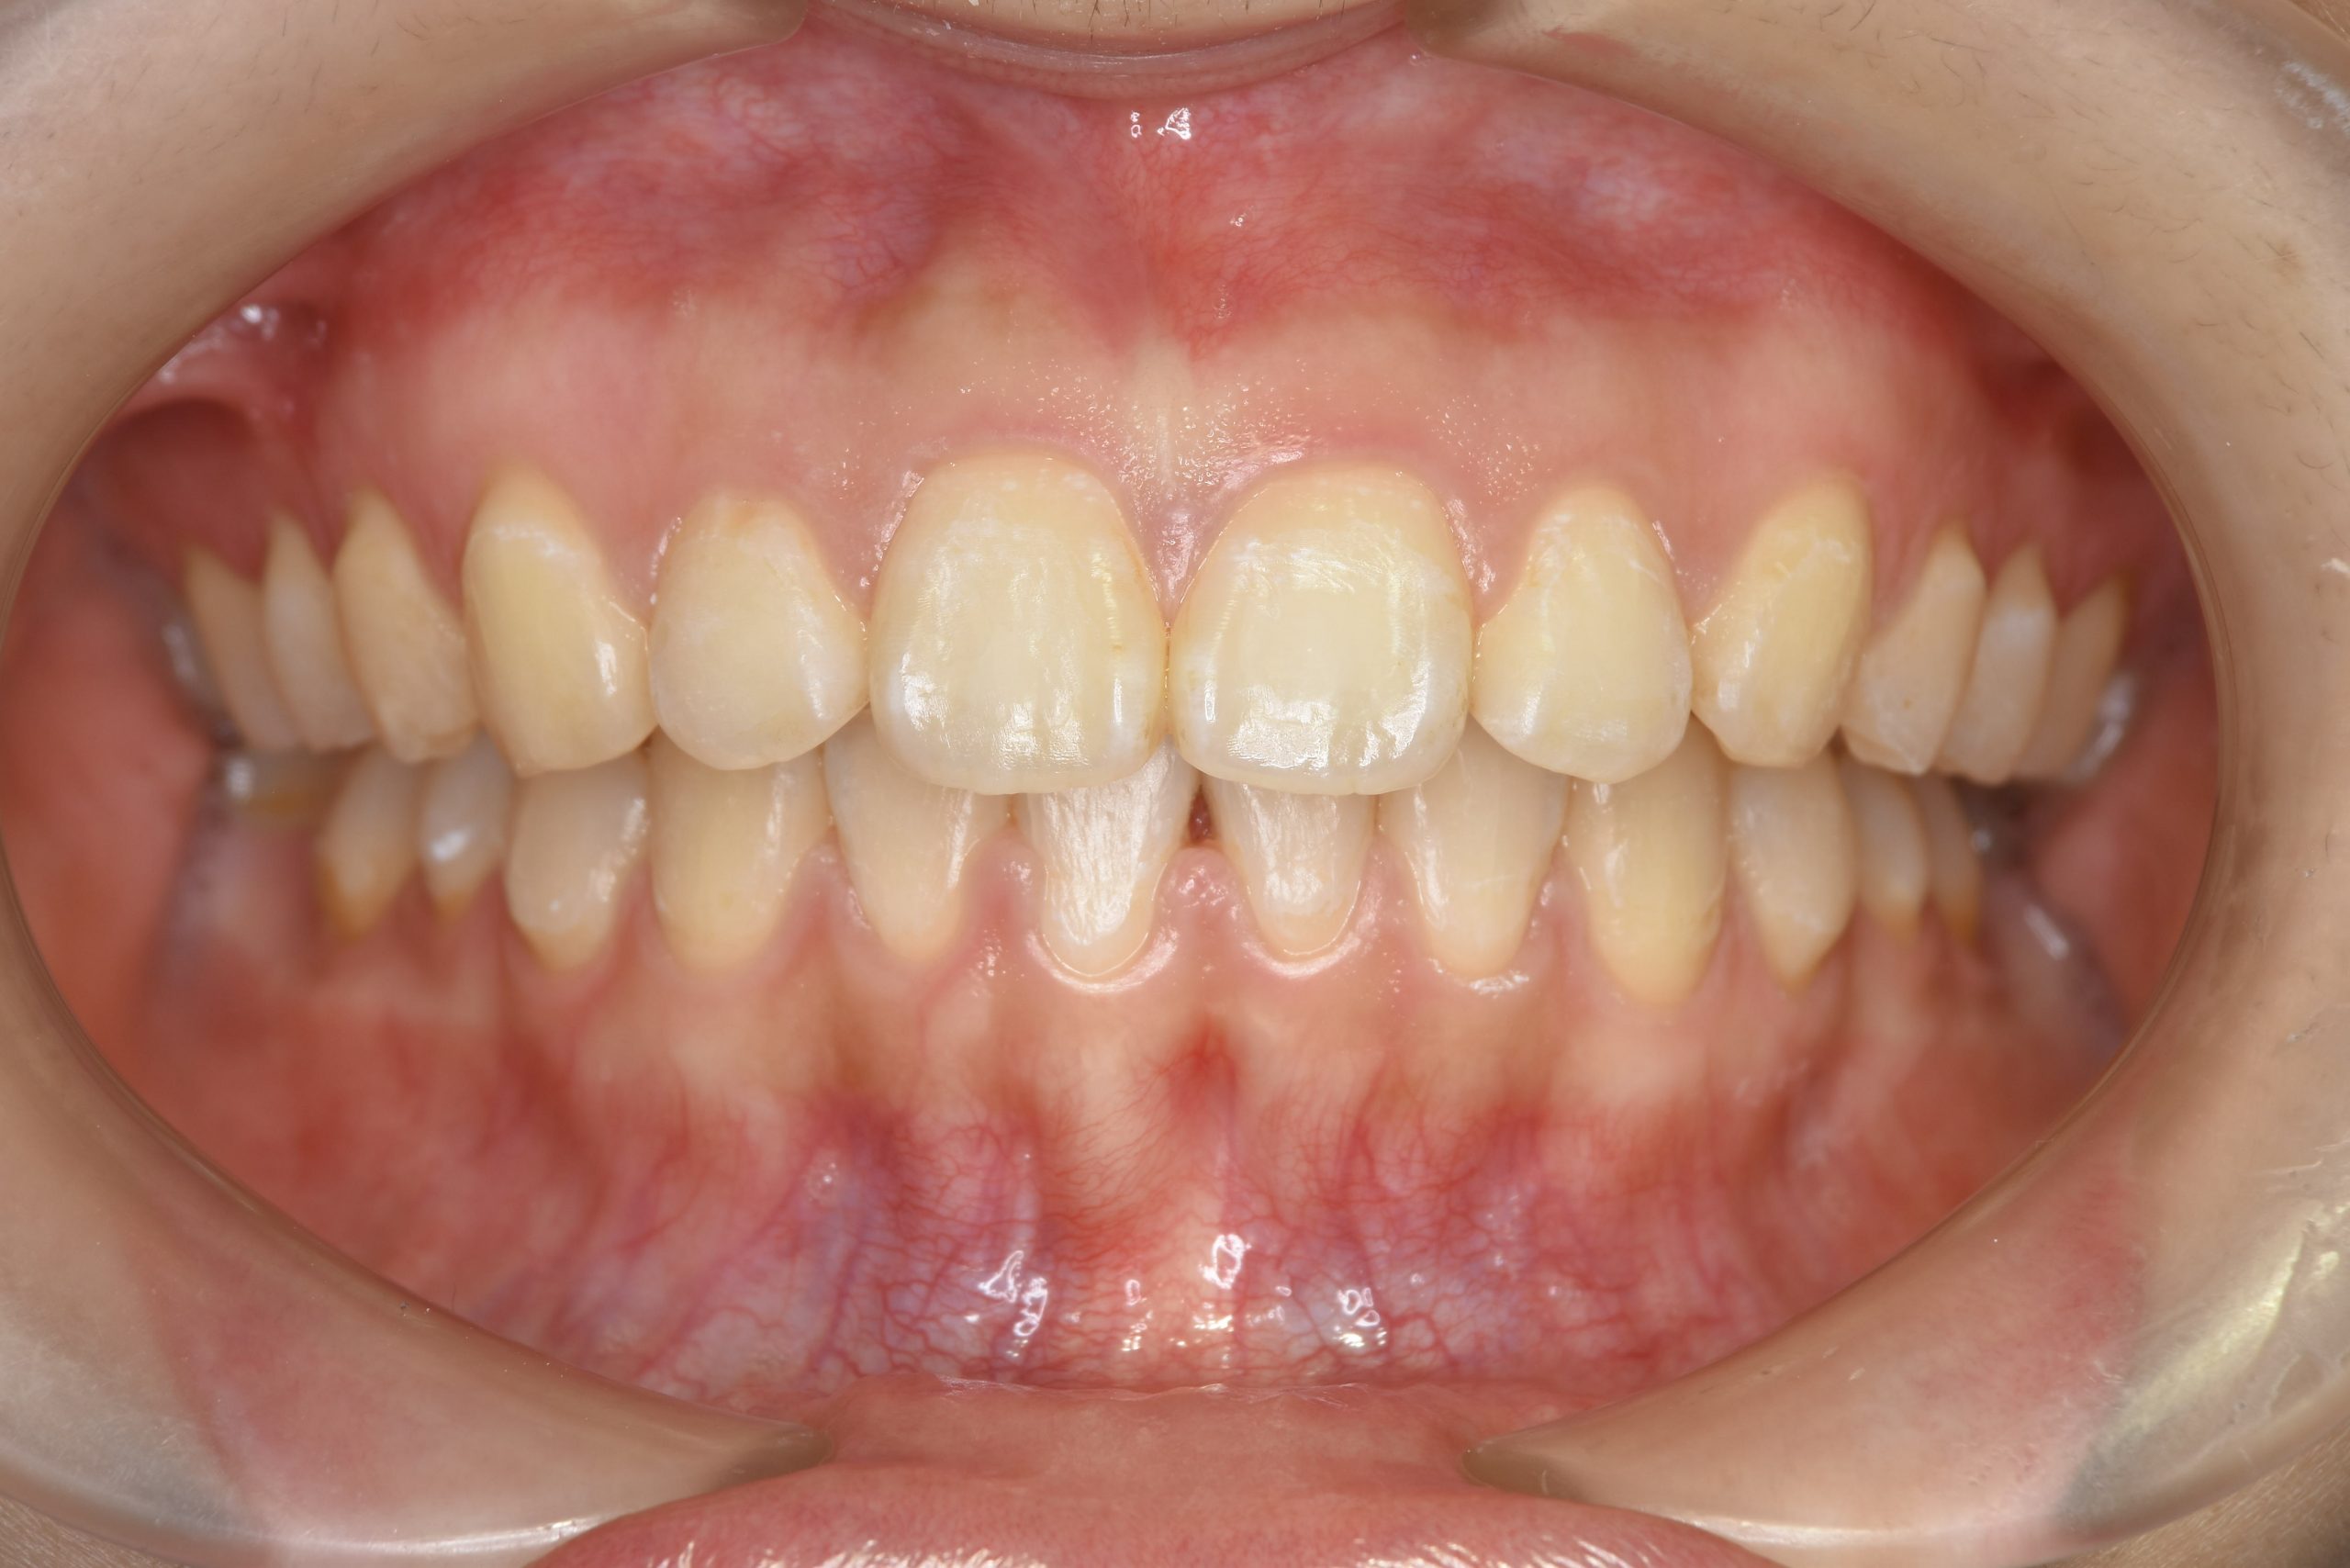

アフター

施術内容 MSEと下顎リンガルアーチを用いて上下顎骨を拡大した。

その後マルチブラケット装置を用いて非抜歯で歯牙を配列し、良好な咬合を獲得した。

治癒期間 3年7か月間